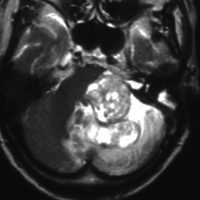

典型的な例1

舌萎縮(舌が右側に曲がっている)に気づいて発見された舌下神経鞘腫です。

舌の右側だけが痩せて萎縮しています,前に出すと麻痺側に曲がります。

舌に波のようなシワができます。

頭蓋底の舌下神経管から頭蓋底部,深頸部に伸びた6cmくらいある大きな舌下神経鞘腫です。舌萎縮以外の症状がないので,手術しないで何年も経過観察していますが大きさは変わりません。右側の画像では内頸動脈が圧迫されていますが,狭窄して血流が悪くなるようなことはありません。